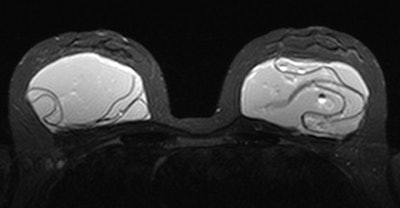

Identification of several visual patterns of collapsed and folded elastomer shell floating in gel: "linguine," "keyhole," "teardrop," "inverted teardrop," and "noose" signs depict silicone visible both inside and outside a radial fold. Image courtesy of Marike Maijers.

Identification of several visual patterns of collapsed and folded elastomer shell floating in gel: "linguine," "keyhole," "teardrop," "inverted teardrop," and "noose" signs depict silicone visible both inside and outside a radial fold. Image courtesy of Marike Maijers.A prospective cohort study out of the Netherlands included 107 women with 214 PIP silicone implants who underwent explantation preceded by short-tau inversion recovery (STIR) MRI. Most of the patients were asymptomatic (70%), and all patients had not previously visited a doctor -- the women wouldn't have been seen if it weren't for the recall, according to Marike Maijers, a doctoral student and resident in plastic surgery at VU University Medical Center in Amsterdam. Maijers wrote her thesis on safety in the imaging of silicone breast implants, with a particular focus on PIP implants.